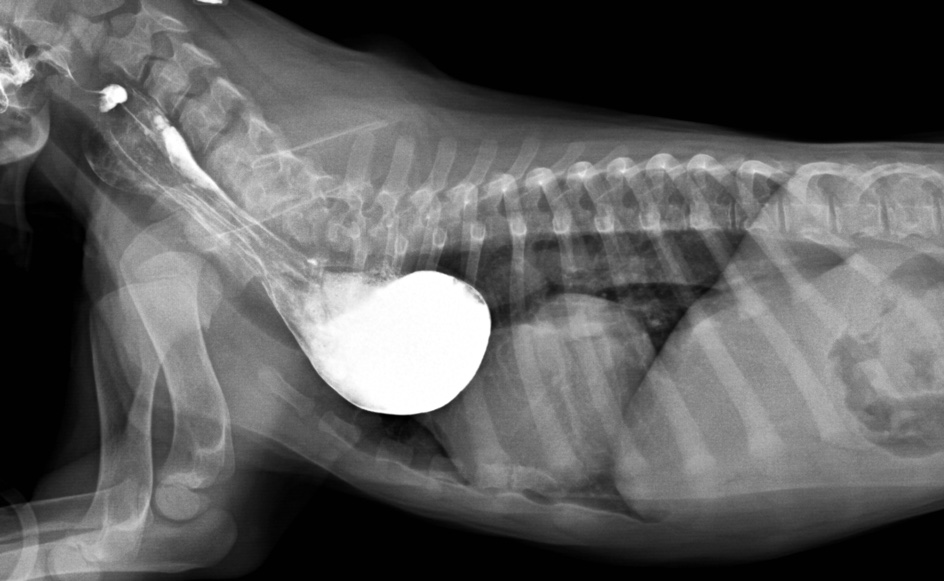

Les radiographies montraient d’abord un élargissement médiastinal marqué par une structure (flèches jaunes) dont l’opacité varie selon la position du chien et qui se confond en grande partie avec la silhouette cardiaque. Sur la latérale droite, elle montre une cavité gazeuse dans sa portion ventrale et une opacité plus liquidienne dorsalement, alors que c’est l’inverse en latérale gauche. Sa portion gauche est remplie de gaz sur la VD et cette zone est entourée d’une paroi d’opacité de tissu mou. La trachée (pointillé orange) est déplacée ventralement et incurvée tout juste devant la silhouette cardiaque sur les latérales, alors qu’elle est déviée focalement vers la gauche et légèrement rétrécie sur la VD. Sur cette même vue, on aperçoit aussi une opacité courbe (pointillé rouge) qui se superpose à la portion crâniale droite de la silhouette cardiaque.

Ces signes radiographiques sont compatibles avec une persistance de la 4e arche aortique qui provoque une compression oesophagienne et une dilatation marquée de sa portion médiastinale crâniale au coeur. Un peu de baryum a été donné pour confirmer la compression de l’oesophage à la base du coeur, mais le déplacement de la trachée vers la gauche sur la VD était déjà diagnostique de la persistance de la 4e arche aortique, comme l’a démontré l’étude de Buchanan (1).